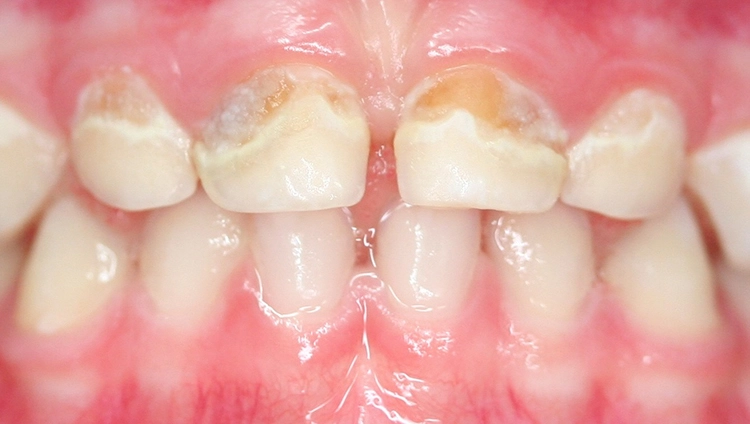

Dr. J. SchmoeckelAbb. 2: Die Frühkindliche Karies (früher „Nuckelflaschenkaries“ genannt) ist durch ein Auftreten flächiger kariöser Läsionen, die meist zunächst die Oberkieferschneidezähne betreffen, gekennzeichnet. Hauptursachen von ECC sind eine mangelhafte Zahnpflege beim Kleinkind in Kombination mit einem hochfrequenten Konsum zuckerhaltiger Getränke zwischendurch und/oder nachts.

Beim Kleinkind spielt primär die frühkindliche Karies eine Rolle, die initial meist durch kariöse Läsionen an den Oberkieferfrontzähnen gekennzeichnet ist (Abb. 2). Im permanenten Gebiss unterliegen die Kauflächen der durchbrechenden 1. und 2. Molaren insbesondere in der ca. 1,5 Jahre dauernden Durchbruchsphase einem erhöhten Kariesrisiko. Während kieferorthopädischer Maßnahmen mit festsitzenden Apparaturen bei Jugendlichen sollte besonderes Augenmerk auf die Beurteilung der Mundhygiene, wie dem Vorhandensein kariogener Plaque auf Kariesrisikoflächen (Abb. 3), und Kariesaktivität gelegt werden, um frühzeitig präventiv einzugreifen und klinische Bilder mit kariösen Läsionen an fast allen Zähnen möglichst zu vermeiden (Abb. 4).